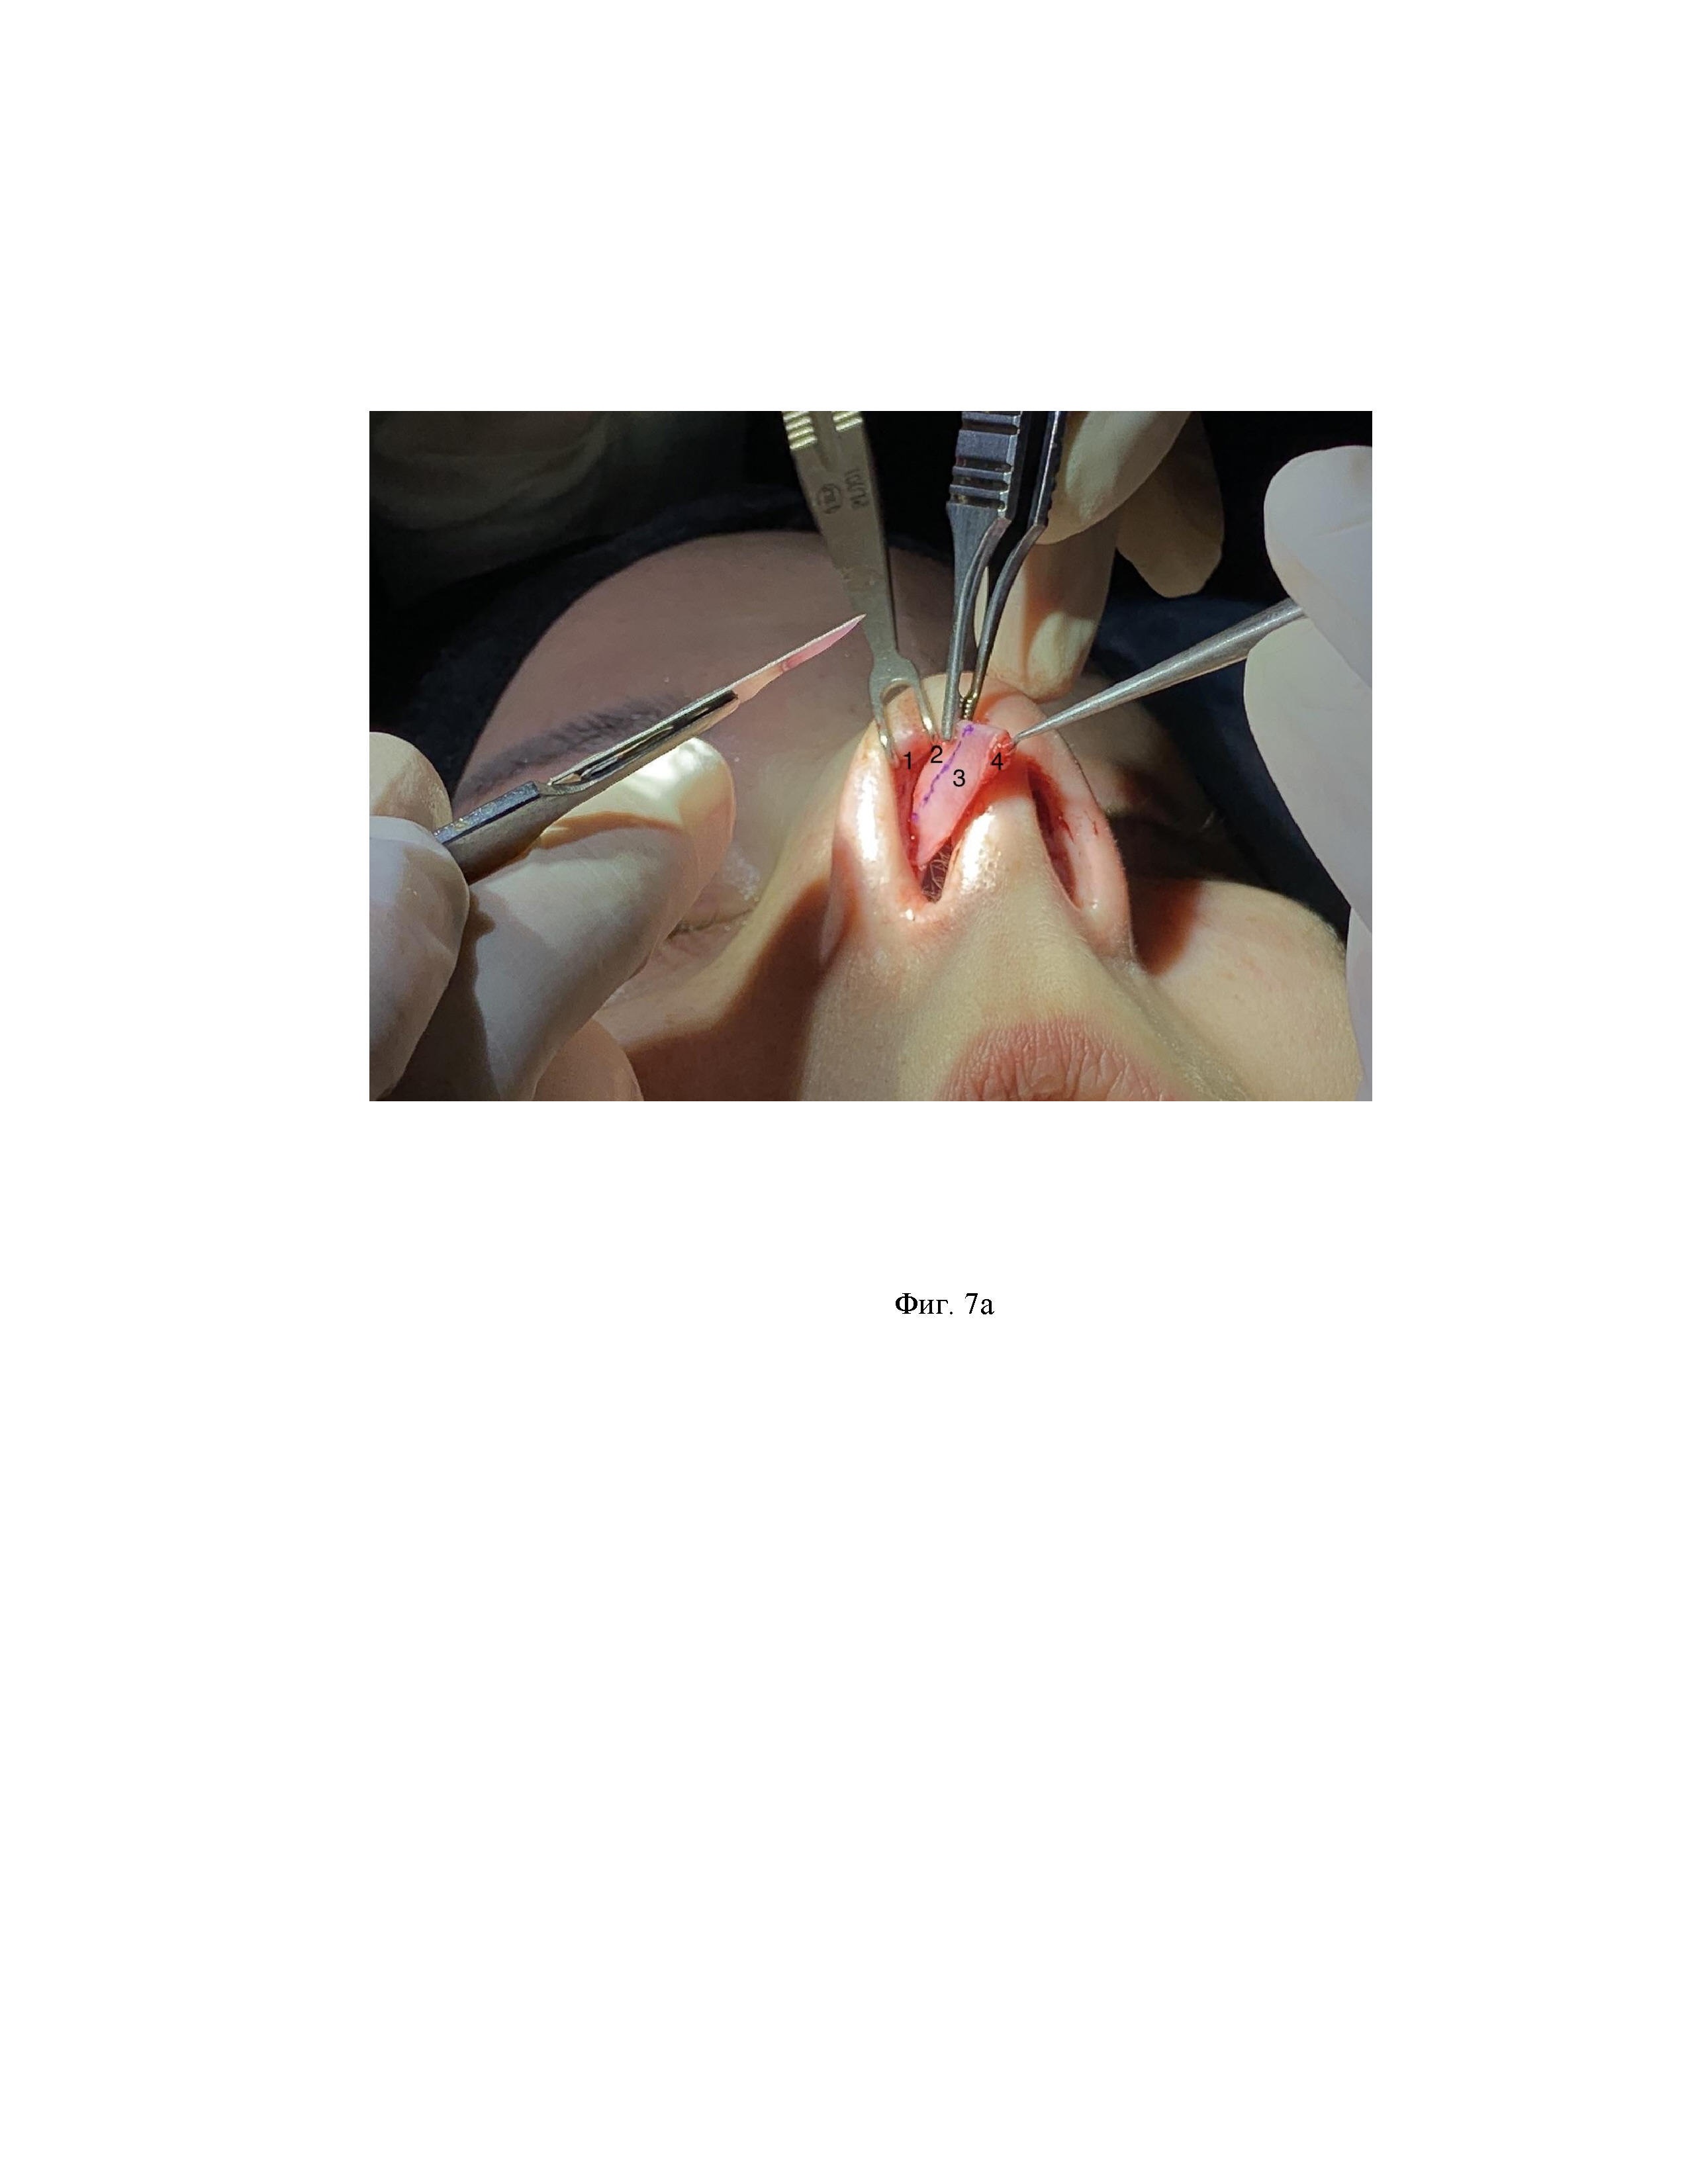

Изобретение относится к медицине, а именно - к пластической хирургии, и может быть использовано при проведении ринопластики, конкретнее - коррекции формы кончика носа. Ринопластика является одной из самых сложных процедур в пластической хирургии, а пластика кончика носа - ее ключевой этап, определяющий функцию и эстетику носа. Изменение анатомической структуры носа в погоне за красотой его очертаний может приводить к функциональным нарушениям наружного и внутреннего носовых клапанов, особенно у пациентов с существующей предрасположенностью их дисфункции, что требует тщательного хирургического планирования. Далее в тексте заявителем приведено разъяснение, которое необходимо для облегчения однозначного понимания сущности заявленных материалов и исключения противоречий и/или спорных трактовок при выполнении экспертизы по существу: Пинч-деформация кончика носа – это сужение кончика носа в области куполов хряща крыла носа, переходящее в вогнутую деформацию латеральной ножки (ЛН). Существующие методы коррекции широкого (например, бульбообразного или коробочного) кончика носа сводятся к резекции цефалического и реже каудального края латеральной ножки (далее - ЛН) хряща крыла носа (нижний латеральный хрящ, или хрящ крыла носа, далее - ХКН). В результате чего, с одной стороны, достигается желаемое сужение кончика носа, с другой стороны - ослабляется структурная опора хряща крыла носа. Поэтому при коррекции широкого кончика носа требуется создать условия хорошей поддержки крыльев носа [Helmut Fischer, Wolfgang Gubisch. Nasal Valves—Importance and Surgical Procedures// Facial plastic surgery. – 2006. - Volume 22, number 4. - Pages 266-280]. Хрящ крыла носа является основным компонентом кончика носа. Конфигурация и стабильность ХКН обеспечивает как внешние очертания кончика носа [Douglas Sidle, Katherine Hicks. Nasal Obstruction Considerations in Cosmetic Rhinoplasty// Journal Otolaryngologic Clinics of North America. - 2018 - Issue number 5. - Pages 987-1002]. https://doi.org/10.1016/j.otc.2018.05.011], так и функцию носовых клапанов, и ослабление латеральной ножки приводит к нежелательным последствиям клапанной дисфункции [Rod J., Joseph Raniere, Richard Y.Ha. The Alar Contour Graft: Correction and Prevention of Alar Rim Deformities in Rhinoplasty// From the university of Texas Southwestern Medical Center. - Received for publication 2001, - March 27. - Pages 2495-2505], [C. Spencer Cochran, David A. Sieber. Extended Alar Contour Grafts: An Evolution of the Lateral Crural Strut Graft Technique in Rhinoplasty// Plastic and Reconstructive Surgery. – 2017. – October. - Pages 559-567], [Amir A. Sazgar, Charles Woodard, Sam P. Most. Preservation of the Nasal Valve Area With a Lateral Crural Hinged Flap: A Cadaveric Study// Aesth Plast Surgery – 2012. – 36. - Pages 244–247]. Слабые латеральные ножки даже при избыточной их ширине не способны обеспечить адекватную поддержку зоны носовых клапанов и способствуют коллапсу внутреннего и наружного носовых клапанов [Henry P. Barham, Anna Knisely, Jenna Christensen, Raymond Sacks, George N. Marcells, Richard J. Harvey. Costal Cartilage Lateral Crural Strut Graft vs Cephalic Crural Turn-in for Correction of External Valve Dysfunction// JAMA Facial Plastic Surgery. - Published online. – 2015. - August 6. - Pages Е1-Е6]. При цефалической резекции ХКН возможным неблагоприятным функциональным и эстетическим последствием является не только ослабление латеральной ножки, но и повреждение зоны связки скролл, которая соединяет ХКН и верхний латеральный хрящ (далее - ВЛХ) и является как главным механизмом поддержки кончика носа [Douglas Sidle, Katherine Hicks. Nasal Obstruction Considerations in Cosmetic Rhinoplasty// Journal Otolaryngologic Clinics of North America. - 2018 - Issue number 5. - Pages 987-1002. https://doi.org/10.1016/j.otc.2018.05.011], так и важным элементом функции носовых клапанов. Разрушение зоны связки скролл способствует ослаблению поддержки кончика носа и значительному нарушению функции внутреннего носового клапана (далее - ВНК) [Jacob G. Unger, Jason Roostaeian, Kevin H. Small, Ronnie A. Pezeshk, Michael R. Lee, Ryan Harris, Rod J. Rohrich. Alar Contour Grafts in Rhinoplasty: A Safe and Reproducible Way to Refine Alar Contour Aesthetics// Alar Contour Grafts in Rhinoplasty. 2015. - Volume 137, Number 1. - Pages 52-61]. А поскольку внутренний (ВНК) и наружный (ННК) носовые клапаны в своем функционировании тесно взаимосвязаны между собой, то, соответственно, проблемы любой из зон носовых клапанов приводит к нарушению дыхания [Amir A. Sazgar, Charles Woodard, Sam P. Most. Preservation of the Nasal Valve Area With a Lateral Crural Hinged Flap: A Cadaveric Study// Aesth Plast Surgery – 2012. – 36. - Pages 244–247]. Из исследованного уровня техники выявлен источник [Rollin K. Daniel, Peter Palhazi. The Nasal Ligaments and Tip Support in Rhinoplasty: An Anatomical Study// Aesthetic Surgery Journal. – 2018. - 1–12] [https://academic.oup.com/asj/advance-article-abstract/doi/10.1093/asj/sjx192/4816879], сущностью которого является подробное описание связочных структур носа, которые играют большую роль в структурной поддержке кончика носа, что является существенным для однозначного понимания достигаемого заявителем технического результата, а именно - сохранение всех связок при заявленном способе, а также дает понимание в различиях между существенными признаками прототипа и заявленного технического решения по отношению к сохранению структурной поддержки кончика носа. Согласно известному техническому решению, среди связок кончика носа важными связками структурной поддержки кончика носа являются связка скролл и связка Питанги. На Фиг.1 – Фиг.3 приведены иллюстрации из известного источника для ясности понимания структурной анатомии связочной системы носа и, соответственно, достигаемого заявителем технического результата. Заявитель поясняет, что фото на Фиг.1 – Фиг.3 и подписи к ним взяты из источника [Rollin K. Daniel, Peter Palhazi. The Nasal Ligaments and Tip Support in Rhinoplasty: An Anatomical Study// Aesthetic Surgery Journal. – 2018. - 1–12] [https://academic.oup.com/asj/advance-article-abstract/doi/10.1093/asj/sjx192/4816879]. Связка скролл (в ориг. описании scroll ligament complex) - это комплекс фиброзных волокон, который составляет лонгитудинальный (продольный) и вертикальный сегменты (части) связки. Лонгитудинальный сегмент связки скролл соединяет верхний латеральный хрящ (ВЛХ) и хрящ крыла носа (ХКН). Таким образом, лонгитудинальный сегмент связки скролл связывает вместе ВЛХ и ХКН. Вертикальный сегмент связки скролл соединяет кожу и мягкие ткани кончика носа с ХКН. Таким образом, вертикальный сегмент связки скролл прикрепляет хрящ крыла носа к коже кончика носа. Обе структуры - лонгитудинальный и вертикальный сегменты связки скролл стабилизируют кончик носа, обеспечивая ему структурную поддержку. На Фиг. 1 представлен лонгитудинальный сегмент связки скролл (в ориг. подписи LSL) (фото А, В). Показана кадаверная диссекция LSL, которая соединяет края верхнего латерального хряща (в ориг. подписи ULC) и хряща крыла носа (в ориг. подписи LLC) (фото С). Демонстрация LSL во время операции на живом человеке (фото D). Схема LSL и заключенного в ее толще сесамовидного хряща. На Фиг. 2 представлен вертикальный сегмент связки скролл (в ориг. подписи VSL) и связки грушевидной апертуры (в ориг. подписи PAL) (фото А). Кадаверная диссекция показывает VSL, соединение между хрящем крыла носа (LLC) и верхним латеральным хрящем ULC и вертикальную связку грушевидного отверстия (в ориг. подписи VPL) между ULC и основанием носа (в ориг. подписи NB) (фото В). Показаны прикрепления VSL и VPL. (фото C, D). Показана схема вертикального сегмента связки скролл (синие точки) и связки грушевидной апертуры (красные точки). Связка Питанги – это связка, ориентированная от внутренней поверхности кожи кончика носа и проходящая тангенциально между хрящами крыльев носа, продолжающаяся в мышцы окружающие нос и рот и вплетающаяся в кожный столбик носа (колумеллу) - является средней частью поверхностной мышечно-апоневротической системы носа. Связка Питанги делится на поверхностный и глубокие слои. Поверхностный слой становится продолжением круговой мышцы рта, глубокая часть вплетается в мышцу-депрессор носовой перегородки. Связка Питанги играет важную роль в поддержке ротации кончика носа [Rollin K. Daniel, Peter Palhazi. The Nasal Ligaments and Tip Support in Rhinoplasty: An Anatomical Study// Aesthetic Surgery Journal. – 2018. - 1–12] [https://academic.oup.com/asj/advance-article-abstract/doi/10.1093/asj/sjx192/4816879]. На Фиг. 3 представлена связка Питанги (фото А, В) - кадаверная диссекция, показывающая разделение поверхностной мышечно-апоневротической системы (розовый) на поверхностную часть (жёлтый), которая продолжается к поверхностной круговой мышце рта и носа (в ориг. подписи SOON) и глубокой части (зеленый), которая продолжается в мышцу-депрессор перегородки носа (в ориг. подписи DSN) (рис. С - схема связки Питанги и ее соединения с мышцами). Таким образом, из известного источника выявлена существенная роль связки скролл, причем как ее лонгитудинального (продольного) сегмента, соединяющего ВЛХ и ХКН, так и вертикального сегмента, прикрепляющей хрящ крыла носа к коже кончика носа, а также сохранения связки Питанги для укрепления структурной поддержки кончика носа. Из исследованного заявителем уровня техники выявлены технические решения, направленные на коррекцию концевых отделов носа и хрящей крыла носа. Так, из исследованного заявителем уровня техники выявлен источник [Süleyman Taє. Superior-Based Transposition Flap: A Novel Technique in Rhinoplasty (Транспозиционный лоскут на верхнем основании: новая техника в ринопластике)// Aesthetic Surgery Journal. - July 2019. - Volume 39. - Issue 7. - Pages 720–732. https://doi.org/10.1093/asj/sjy197]. Сущностью является следующая хирургическая методика. Операцию выполняют из закрытого доступа, без разреза колумеллы чрезхрящевым разрезом по каудальному краю латеральной ножки ХКН. Далее выполняют поднадхрящничную диссекцию ХКН с сохранением целостности соединения верхнего и нижнего латеральных хрящей. По линии предварительной разметки вдоль по латеральной ножке выполняют ее рассечение, не затрагивая подлежащие мягкие ткани и кожу, оставляя 6 мм каудальной порции хряща крыла носа. Цефалическую порцию ХКН отделяют от подлежащих мягких тканей до соединения с верхним латеральным хрящом (зона связки скролл) и переносят вперед, на наружную поверхность латеральной ножки по типу «накладки», где закрепляют матрасными швами 5/0 полидиоксанона через все слои, включая кожу внутренней высылки крыла носа и дубликату крыльных хрящей. Недостатками известного технического решения являются: - нарушение рельефа передней поверхности латеральной ножки, что приводит к утолщению в проекции крыльного хряща на коже и сглаживает дефиницию кончика носа, включая крыльную борозду, по сравнению с заявленным способом, в котором хрящевой лоскут находится на задней поверхности латеральной ножки; - отслойка от подлежащей ткани верхней части латеральной ножки при перемещении лоскута, что усложняет оперативный прием, создает риски травмирования внутренней выстилки носа и самого хряща, по сравнению с заявленным техническим решением, где отделение перемещаемого хрящевого лоскута от подлежащих тканей не требуется; - после перемещения хрящевого лоскута и его фиксации, верхний край оставленной каудальной полоски хряща, несущей каркас крыла носа, остается без возможности корректировки, симметризации в процессе операции. В случае необходимости симметризации потребуется снимать швы и отделять перемещенный лоскут, в отличие от заявленного технического решения, где верхний край ХКН доступен коррекции на любом этапе операции; - фиксация лоскута проходит через все слои (хрящ, мягкие ткани, кожу внутренней высылки крыла носа) длительно рассасывающемся шовным материалом, что создает риск инфицирования и образования лигатурных свищей. Из исследованного заявителем уровня техники выявлен источник [Güncel Oztürk. Scroll Ligament Preservation and Improvement in Nasal Tip with the Room Concept// Aesthetic Plastic Surgery. – 2019. - Pages 124-133]. [https://link.springer.com/article/10.1007%2Fs00266-019-01436-z]. Сущностью известного технического решения является следующая хирургическая методика. Внутриносовым доступом без разреза колумеллы выполняют отслойку хряща крыла носа (ХКН). Далее латеральную ножку рассекают на всем протяжении с сохранением ее каудальной части 6 мм. Выполняют диссекцию под кожей преддверия латеральной ножки. Часть цефалического сегмента резецируют и культю сохранившейся цефалической части латеральной ножки вшивают под каудальную полоску ХКН. Недостатками известного технического решения является то, что при его осуществлении: - удаляют часть хряща, ослабляя конструкцию крыла носа по сравнению с заявленным техническим решением, при котором весь верхний (цефалический) сегмент латеральной ножки смещают в качестве укрепляющего трансплантата, усиливая конструкцию крыла носа и увеличивая просвет наружного носового клапана при сохранении просвета внутреннего носового клапана; - смешение хрящевого лоскута идет лишь в переднем направлении, в отличие от заявленного технического решения, где смешение хрящевого лоскута идет в передне-медиальном направлении, что позволяет использовать часть хрящевого лоскута для укрепления области купола носа, что, соответственно, позволяет избежать пинч-деформации кончика носа, что особенно актуально при слабых и тонких куполах ХКН; - натяжение связки скролл идет лишь в переднем направлении, в отличие от заявленного технического решения, где натяжение связки скролл идет по ходу ее волокон - в передне-медиальном направлении, что усиливает механизм поддержки купола кончика носа; - отслойка резецируемого сегмента хряща может привести к перфорации внутренней выстилки латеральной ножки, что повышает риск инфицирования из носовой полости, при этом продлевается время операции. Наиболее близким к заявленному техническому решению по совокупности существенных признаков и по назначению, выбранным заявителем в качестве прототипа, является источник [Ozmen S. Sliding Alar Cartilage (SAC) Flap A New Technique for Nasal Tip Surgery// Annals of Plastic Surgery. - November 2009. - Volume 63. - Number 5], сущностью является способ уменьшения ширины кончика носа, включающий в себя выделение и обнажение хрящевых структур носа, в том числе латеральной ножки ХКН с пересечением колумеллы (кожного столбика носа), рассечение хряща латеральной ножки вдоль ее хода от купола кончика носа до латерального края с оставлением каудального сегмента латеральной ножки шириной 5-6 мм, при этом цефалический (верхний) сегмент латеральной ножки не удаляют, а перемещают спонтанно под каудальный сегмент латеральной ножки в предварительно сформированный карман с помощью отслойки кожи и слизистой внутренней выстилки латеральной ножки, далее производят фиксацию цефалического и каудального сегментов латеральной ножки между собой посредством хирургической нити 5/0 из полиоксидония 1-2 сквозными швами через все слои, включая слизистую оболочку внутренней выстилки латеральной ножки с завязыванием узлов этой нити в полости носа на слизистой. Недостатками прототипа по сравнению с заявленным техническим решением являются: - недостаточное натяжение лонгитудинального (продольного) сегмента связки скролл вследствие того, что перемещение цефалических сегментов под каудальные сегменты латеральной ножки идет спонтанно, в отличие от заявленного технического решения, в котором цефалические сегменты перемещают под каудальные в передне-медиальном направлении (в направлении горизонтального компонента связки скролл), благодаря чему увеличивается натяжение горизонтального компонента связки скролл, создавая профилактику ее складывания, образования дупликатуры и утолщения в зоне внутреннего носового клапана, создавая при этом дополнительное натяжение от кожного чехла носа, верхнего латерального хряща к структурам кончика носа, усиливая соответственно поддержку ротации кончика носа. - недостаточное усиление купола ХКН вследствие того, что цефалический сегмент латеральной ножки не перемещают под купол ХКН, в отличие от заявленного технического решения, в котором цефалический сегмент служит не только усилителем каудального сегмента латеральной ножки, но и дополнительно усиливает купол ХКН, поскольку его (цефалический сегмент) перемещают в том числе под купол, что усиливает профилактику деформации кончика носа «пинч» (то есть по типу носа, пережатого прищепкой). - большая вероятность образования лигатурных свищей носа и его инфицирования вследствие того, что фиксацию цефалического и каудального сегментов латеральной ножки между собой производят посредством длительно рассасывающейся хирургической нити 5/0 из полиоксидония 1-2 сквозными швами через все слои, включая слизистую оболочку внутренней выстилки латеральной ножки с завязыванием узлов этой нити в полости носа на слизистой с формированием ее гофрирования, что создает большую по сравнению заявленным техническим решением вероятность образования лигатурных свищей носа и его инфицирования, так как известно, что нить полиоксидония рассасывается от 6 до 12 месяцев. В заявленном техническом решении длительно рассасывающейся нитью, например, 5/0 полиоксидония, фиксируют лишь соединение верхнего и нижнего латеральных хрящей, проходя только через хрящевую ткань обеих сегментов, связывая каудальный сегмент ХКН с цефалическим и формируя укрепленный каркас крыла носа, не захватывая при этом мягкие ткани, кожу и слизистую внутренней выстилки ЛН. Отслоенную кожу и слизистую внутренней выстилки латеральной ножки фиксируют быстро рассасывающимися (7-10 дней) швами, например, 6/0 викрил через оба сегмента хрящей латеральной ножки. - больший дискомфорт у пациента на протяжении более чем полугода в послеоперационном периоде вследствие того, что в полости носа на слизистой латеральной ножки завязывают узлы из плотной, длительно рассасывающейся (6-12 месяцев) нити из полиоксидония, в отличие от заявленного технического решения, где используют более комфортную, быстро рассасывающуюся (7-10 дней) хирургическую нить, например, викрил-рапид 6/0. - гофрирование (сморщивание) слизистой при завязывании длительно рассасывающейся нити через все слои (каудальный и цефалический сегменты латеральной ножки, слизистая), что может оказывать влияние на точность сопоставления краев разреза слизистой оболочки носа. В заявленном техническом решении слизистая оболочка не повреждается и ее ушивание идет точно с сопоставлением краев разреза. - большая травматичность вмешательства, так как операция сопровождается пересечением колумеллы с последующим зашиванием ее кожи и, следственно, возможным образованием рубцовой ткани, разрушением связки Питанги и вертикального компонента связки скролл, которые являются важными анатомическими образованиями носа и выполняют его структурную, опорную функцию, в отличие от заявленного технического решения, где доступ к хрящу происходит с минимальной травматичностью, так как колумеллу не пересекают, что обеспечивает отсутствие на ней рубцовой ткани, связку Питанги не затрагивают и вертикальные компоненты связки скролл, идущие от мягкотканного чехла кончика носа к ХКН, остаются интактными и не повреждаются. Техническим результатом заявленного технического решения является устранение недостатков прототипа путем разработки способа уменьшения ширины кончика носа с усилением его купола, а также с сохранением связок Питанги и скролл путем цефалической резекции ХКН с укреплением латеральных ножек без изменения рельефа их передней поверхности и усилением механизма поддержки кончика носа интактным соединением верхних и нижних латеральных хрящей в зоне связки скролл, усиления купола носа путем смещения цефалического сегмента ХКН в передне-медиальном направлении, в результате чего достигается: - большее натяжение лонгитудинального (продольного) сегмента связки скролл вследствие того, что перемещение цефалических сегментов под каудальные сегменты латеральной ножки идет в передне-медиальном направлении, совпадающем с направлением лонгитудинального сегмента связки скролл, создавая профилактику складывания связки скролл, образования дупликатуры и утолщения в зоне внутреннего носового клапана, создавая при этом дополнительное натяжение от кожного чехла носа, верхнего латерального хряща к структурам кончика носа, усиливая соответственно поддержку ротации кончика носа. - усиление купола ХКН вследствие того, что цефалический сегмент латеральной ножки перемещают в том числе под купол ХКН, что дополнительно усиливает купол и, соответственно, усиливает профилактику деформации кончика носа «пинч» (то есть по типу носа, пережатого прищепкой). - меньшая вероятность образования лигатурных свищей носа и его инфицирования вследствие того, что длительно рассасывающейся (6-12 месяцев) хирургической нитью, например, 5/0 или 6/0 полиоксидония, фиксируют лишь соединение верхнего и нижнего латеральных хрящей, проходя только через хрящевую ткань обоих сегментов, связывая каудальный сегмент ХКН с цефалическим и формируя укрепленный каркас крыла носа, не захватывая при этом мягкие ткани, кожу и слизистую внутренней выстилки ЛН. Отслоенную кожу и слизистую внутренней выстилки латеральной ножки фиксируют быстро рассасывающейся (7-10 дней) нитью, например, 6/0 викрил-рапид, через оба сегмента хрящей латеральной ножки с захватом мягких тканей, кожи и слизистой внутренней выстилки ноздри. - меньший дискомфорт у пациента в послеоперационном периоде вследствие того, что в полости носа на слизистой латеральной ножки для завязывания узлов используют более комфортную, быстро рассасывающуюся (7-10 дней) хирургическую нить, например, викрил-рапид 6/0. - отсутствие гофрирования (сморщивания) слизистой, так как мягкие ткани, кожу и слизистую внутренней выстилки ЛН завязывают быстро рассасывающейся нитью, например, викрил-рапид 6/0, вследствие чего слизистая оболочка не повреждается и ее ушивание идет точно с сопоставлением краев разреза. - меньшая травматичность вмешательства, так как колумеллу не пересекают, что обеспечивает отсутствие на ней рубцовой ткани, связку Питанги не затрагивают и вертикальные компоненты связки скролл, идущие от мягкотканного чехла кончика носа к ХКН, остаются интактными и не повреждаются. Сущностью заявленного технического решения является способ уменьшения ширины кончика носа с укреплением купола и латеральных ножек хрящей крыльев носа с сохранением связок Питанги и скролл, заключающийся в том, что выполняют поднадхрящничную отслойку хряща крыла носа доступом через его под- или чрезхрящевой разрез, выполняют разметку на расстоянии 6-7 мм от каудального края латеральной ножки, по линии разметки выполняют продольное рассечение латеральной ножки, не затрагивая подлежащие мягкие ткани и кожу, оставляя 6-7 мм каудального сегмента хряща крыла носа, далее на внутренней стороне каудального сегмента хряща крыла носа и купола хряща крыла носа создают карман путем отслойки кожи и слизистой внутренней выстилки каудального сегмента латеральной ножки и купола хряща крыла носа, в карман перемещают цефалический сегмент хряща крыла носа без отделения от подлежащих тканей и резекции, перемещение цефалического сегмента хряща крыла носа производят в передне-медиальном направлении, при этом перемещают медиальный край цефалического сегмента латеральной ножки под купол хряща крыла носа с возможностью укрепления купола, далее формируют укрепленный каркас крыла носа, для чего фиксируют соединение цефалического и каудального сегментов латеральных хрящей длительно рассасывающейся нитью, проходя через хрящевую ткань обеих сегментов, не захватывая мягкие ткани, кожу и слизистую внутренней выстилки ноздри, далее отслоенную кожу и слизистую внутренней выстилки крыла носа фиксируют быстрорассасывающейся нитью через оба сегмента хрящей латеральной ножки с захватом мягких тканей, кожи и слизистой внутренней выстилки ноздри. Заявленное техническое решение иллюстрируется Фиг.1 – Фиг.12. На Фиг.1 – Фиг.3 приведены иллюстрации из источника [Rollin K. Daniel и соавт. (см. The Nasal Ligaments and Tip Support in Rhinoplasty: An Anatomical Study, Aesthetic Surgery Journal 2018, 1–12)]: На Фиг. 1 представлен лонгитудинальный (продольный) сегмент связки скролл (в ориг. подписи LSL) (фото А, В). Показана кадаверная диссекция LSL, которая соединяет края верхнего латерального хряща (в ориг. подписи ULC) и хряща крыла носа (в ориг. подписи LLC) (фото С). Демонстрация LSL во время операции на живом человеке (фото D). Схема LSL и заключенного в ее толще сесамовидного хряща. На Фиг. 2 представлен вертикальный сегмент связки скролл (в ориг. подписи VSL) и связки грушевидной апертуры (в ориг. подписи PAL) (фото А). Кадаверная диссекция показывает VSL, соединение между хрящем крыла носа (LLC) и верхним латеральным хрящем ULC и вертикальную связку грушевидного отверстия (в ориг. подписи VPL) между ULC и основанием носа (в ориг. подписи NB) (фото В). Показаны прикрепления VSL и VPL. (фото C, D). Показана схема вертикальной связки скролл (синие точки) и связки грушевидной апертуры (красные точки). На Фиг. 3 представлена связка Питанги (фото А, В) - кадаверная диссекция, показывающая разделение поверхностной мышечно-апоневротической системы (розовый) на поверхностную часть (желтый), которая продолжается к поверхностной круговой мышце рта и носа (в ориг. подписи SOON) и глубокой части (зеленый), которая продолжается в мышцу-депрессор перегородки носа (в ориг. подписи DSN) (рис. С - схема связки Питанги и ее соединения с мышцами). На Фиг.4 представлено фото чрезхрящевого внутриносового разреза по каудальному (нижнему) краю латеральной ножки ХКН. На Фиг.5 представлено фото поднадхрящничной отслойки латеральной ножки ХКН. На Фиг.6 представлено фото отслойки медиальных ножек и куполов ХКН. На Фиг.7 представлены фото: 7а - рассечение латеральной ножки (ЛН) ХКН по линии разметки с оставлением каудального сегмента хряща шириной 6 мм, где 1 - зона связки скролл; 2 - цефалический сегмент ЛН; 3 - каудальный сегмент ЛН; 4 - кожа и слизистая внутренней выстилки ЛН; 7б – ЛН рассечена на два сегмента - цефалический (2) и каудальный (3), видна связка скролл (1); На Фиг.8 представлено фото, на котором показано, что цефалический сегмент ЛН (2) на связке скролл (1) перемещается в карман из кожи и слизистой внутренней выстилки (4) под каудальный сегмент ЛН (3); На Фиг. 9 представлено фото, где виден каудальный сегмент ЛН (3) под который перемещен цефалический сегмент ЛН на связке скролл (1). Конструкция фиксирована матрасными швами, проходящими через цефаллический и каудальный сегменты ЛН длительно рассасывающейся нитью. ЛН усилена и стала прямой; На Фиг.10 представлены фото: 10а - вид кончика носа и просвета наружного носового клапана до операции. Кончик носа широкий. Каудальные сегменты ЛН вывихнуты в просвет ноздрей, за счет чего сужен просвет наружных носовых клапанов. 10б - вид кончика носа и просвета наружного носового клапана после операции. Вывих каудальных сегментов ЛН устранен, просвет наружных носовых клапанов увеличен. Кончик носа стал узким. На Фиг.11 представлено фото коробкообразного асимметричного и опущенного кончика носа по Примеру 1. Результат до ринопластики и через 12 месяцев после ринопластики. На Фиг.12 представлено фото бульбообразного широкого и опущенного кончика носа по Примеру 2. Результат до ринопластики и через 12 месяцев после ринопластики. Далее заявителем приведено описание осуществления заявленного технического решения: Выполняют поднадхрящничную отслойку хряща крыла носа доступом через его под- или чрезхрящевой разрез, для чего берут скальпель № 15 и выполняют разрез кожи и хряща крыла носа в зоне будущей разметки хряща. Далее продолжают обычный краевой разрез, который распространяется вниз по краю латеральной ножки хряща крыла носа (ХКН) и вверх, проходя по краю купола к латеральным краям медиальных ножек. Далее берут скальпель № 11 и надсекают надхрящницу (Фиг.4), после чего проводят отслойку надхрящницы от латеральных и медиальных ножек ХКН тонким распатором и деликатными ножницами (Фиг.5, 6). После выполнения поднадхрящничной отслойки ХКН доступом через его под- или чрезхрящевой разрез выполняют разметку на расстоянии 6-7 мм от каудального края латеральной ножки, по линии разметки по выполняют продольное рассечение латеральной ножки, не затрагивая подлежащие мягкие ткани, оставляя 6-7 мм каудального сегмента хряща крыла носа, в зависимости от морфотипа лица пациента (Фиг. 7а,б). Далее на внутренней стороне каудального сегмента ЛН хряща крыла носа и купола хряща крыла носа создают карман путем отслойки кожи и слизистой внутренней выстилки каудального сегмента латеральной ножки и купола хряща крыла носа. В образовавшийся карман перемещают цефалический сегмент хряща крыла носа без отделения от подлежащих тканей и резекции, сохраняя целостность хряща, при этом весь цефалический сегмент латеральной ножки идет под каудальный сегмент (Фиг. 8), усиливая конструкцию крыла носа, выступая в качестве укрепляющего трансплантата. При этом перемещение производят в передне-медиальном направлении. Таким образом, цефалический сегмент латеральной ножки оказывается не только под каудальным сегментом латеральной ножки, но и под куполом хряща крыла носа, укрепляя купол. Это позволяет избежать пинч-деформации кончика носа, что особенно актуально при слабых латеральных ножках и куполах ХКН. При этом происходит натяжение лонгитудинального (продольного) сегмента связки скролл в медиально-переднем направлении, что усиливает механизм поддержки кончика носа. Далее формируют укрепленный каркас крыла носа, для чего соединение цефалического и каудального сегментов латеральной ножки фиксируют швами, например, тремя матрасными швами из длительно рассасывающейся нити, например, 5/0 или 6/0 полидиоксанона (в зависимости от толщины крыльных хрящей). При этом швы не проходят все слои крыла носа и не захватывают мягкие ткани, кожу и слизистую внутренней выстилки ноздри, а захватывают соединение цефалического и каудального сегментов латеральных хрящей, проходя через хрящевую ткань обеих сегментов, при этом связывают каудальный сегмент с цефалическим, формируя укрепленный каркас крыла носа (Фиг. 9). Отслоенную кожу, мягкие ткани и кожу и слизистую внутренней выстилки крыла носа фиксируют через оба сегмента хрящей латеральной ножки, например, тремя матрасными чрезхрящевыми швами быстрорассасывающейся нитью, например, 6/0 викрил-рапид для избежания инфицирования и образования лигатурных свищей, а также предотвращения гофрирования слизистой. Далее выполняют формирование купола носа общеизвестными чрезкупольными п-образными швами, фиксируют их между собой и устанавливают хрящевой укрепляющий трансплантат колумеллы по общеизвестной методике. Далее хрящи крыла носа вставляют обратно в ноздри, под кожу кончика носа, края разрезов кожи и внутренней выстилки ушивают отдельными, например, узловыми швами, быстро рассасывающейся нитью, например, 6/0 викрил-рапид (Фиг. 10б). Полость носа тампонируют и устанавливают лангету на наружный нос. На Фиг.10а представлен вид кончика носа и просвета наружного носового клапана до операции. Кончик носа широкий. Каудальные сегменты ЛН вывихнуты в просвет ноздрей, за счет чего сужен просвет наружных носовых клапанов. На Фиг.10б представлен вид кончика носа и просвета наружного носового клапана после операции. Вывих каудальных сегментов ЛН устранен, просвет наружных носовых клапанов увеличен. Кончик носа стал узким. Этим операция завершается. Заявитель поясняет, что при заявленном способе при сохранении целостности хряща не происходит перфорация внутренней выстилки латеральной ножки, что, соответственно, снижает риск инфицирования из носовой полости, при этом сокращается время операции. Заявленный способ использован с положительным результатом при первичных случаях ринопластики у 64 пациентов (49 женщин и 15 мужчин). Срок наблюдения составил от 12 до 18 месяцев после операции. У всех пациентов наблюдали хороший эстетический результат коррекции бульбообразного и коробкообразного типов кончика носа и стабильность латеральных ножек без потери ротации кончика носа. У 11 пациентов заявленный способ позволил коррегировать вогнутую, у 8 выгнутую деформацию, у 5 сложную смешанную волнообразную деформацию латеральных ножек. У всех пациентов укреплен купол кончика носа. У всех пациентов отсутствовало гофрирование слизистой, наблюдалось быстрое заживление слизистой без образования лигатурных свищей и инфицирования. Далее заявителем приведены примеры конкретного выполнения заявленного технического решения. Пример 1. Проведение ринопластики коробкообразного асимметричного и опущенного кончика носа с утолщенными ХКН. Пациентка 38 лет, обратилась по поводу коробкообразного асимметричного и опущенного кончика носа. Проведена ринопластика заявленным способом. Результат приведен на Фиг. 11. На фото 11а видно, что до операции (фото слева) кончик носа асимметричный, искривленный вправо и опущенный. ЛН имеют сложную вогнуто-выгнутую форму. На фото 11б – результат через 12 месяцев после операции. Видно, что кончик носа стал ровный, симметричный, утонченной формы, нивелировано его искривление вправо. ЛН стали одинаковой формы, кончик носа приподнят. Пример 2. Проведение ринопластики бульбообразного широкого и опущенного кончика носа. Пациентка 42 года, обратилась по поводу бульбообразного широкого и опущенного кончика носа. Проведена ринопластика заявленным способом. Одновременно пациентке проведено увеличение губ методом хейлопластики и подтяжка средней зоны лица. Результат приведен на Фиг. 12. На фото 12а видно, что до операции (фото слева) кончик носа был скругленный в форме луковицы (бульбообразный) и опущенный, с плохой поддержкой ротации. На фото 12б – результат через 12 месяцев после операции. Видно, что кончик носа стал тоньше и приобрел более эстетический вид, опущение кончика носа устранено. Таким образом, из описанного выше можно сделать вывод, что заявителем достигнуты поставленные цели и заявленный технический результат, а именно - разработан способ уменьшения ширины кончика носа, укрепления и улучшения формы хрящей крыла носа с сохранением связок Питанги и скролл путем цефалической резекции ХКН с укреплением латеральных ножек без изменения рельефа их передней поверхности и усилением механизма поддержки кончика носа интактным соединением верхних и нижних латеральных хрящей в зоне связки скролл, усиления купола носа путем смещения медиальной части цефалического сегмента ХКН под купол носа в передне-медиальном направлении, при котором достигнуто: - большее натяжение лонгитудинального (продольного) сегмента связки скролл вследствие того, что перемещение цефалических сегментов под каудальные сегменты латеральной ножки идет в передне-медиальном направлении, создавая профилактику ее складывания, образования дупликатуры и утолщения в зоне внутреннего носового клапана, создавая при этом дополнительное натяжение от кожного чехла носа, верхнего латерального хряща к структурам кончика носа, усиливая соответственно поддержку ротации кончика носа. - усиление купола ХКН вследствие того, что цефалический сегмент латеральной ножки перемещают в том числе под купол ХКН, что дополнительно усиливает купол и, соответственно, усиливает профилактику деформации кончика носа «пинч» (то есть по типу носа, пережатого прищепкой). - меньшая вероятность образования лигатурных свищей носа и его инфицирования вследствие того, что длительно рассасывающейся хирургической нитью, например, 5/0 полиоксидония, фиксируют лишь соединение верхнего и нижнего латеральных хрящей, проходя только через хрящевую ткань обоих сегментов, связывая каудальный сегмент ХКН с цефалическим и формируя укрепленный каркас крыла носа, не захватывая при этом мягкие ткани, кожу и слизистую внутренней выстилки ЛН. Отслоенную кожу и слизистую внутренней выстилки латеральной ножки фиксируют быстро рассасывающейся (7-10 дней) нитью, например, 6/0 викрил-рапид, через оба сегмента хрящей латеральной ножки. - меньший дискомфорт у пациента в послеоперационном периоде вследствие того, что в полости носа на слизистой латеральной ножки для завязывания узлов используют более комфортную, быстро рассасывающуюся (7-10 дней) хирургическую нить викрил-рапид 6/0. - отсутствие гофрирования (сморщивания) слизистой, так как мягкие ткани, кожу и слизистую внутренней выстилки ЛН завязывают быстро рассасывающейся нитью, вследствие чего слизистая оболочка не повреждается и ее ушивание идет точно с сопоставлением краев разреза. - меньшая травматичность вмешательства, так как колумеллу не пересекают, что обеспечивает отсутствие на ней рубцовой ткани, связку Питанги не затрагивают и вертикальные компоненты связки скролл, идущие от мягкотканного чехла кончика носа к ХКН, остаются интактными и не повреждаются. Использование заявленного способа является эффективным приемом, дающим хороший эстетический результат при коррекции утолщенной каудальной части ХКН, широкого кончика носа с усилением механизма поддержки ротации кончика носа, укреплением купола кончика носа, укреплением латеральных ножек, сохранением зоны связки скролл и усилением ее натяжения в передне-медиальном направлении по ходу расположения ее волокон, сохранением связки Питанги. Заявленный способ способен предотвратить дисфункцию носовых клапанов, вызванных ослаблением хряща крыла носа и разрушением соединения верхних и нижних латеральных хрящей при снижении травматичности операции и повышении комфортности пациента в послеоперационный период. Заявленное техническое решение соответствует условию патентоспособности «новизна», предъявляемому к изобретениям, так как из исследованного уровня техники не выявлены технические решения, обладающие заявленной совокупностью признаков, приведенных в независимом пункте формулы изобретения, обеспечивающих достижение заявленных результатов. Заявленное техническое решение соответствует условию патентоспособности «изобретательский уровень», предъявляемому к изобретениям, так как, по мнению заявителя, разработан принципиально новый, неочевидный для специалиста из данной области техники, способ с неизвестной до даты представления настоящей заявки совокупностью существенных признаков, дающих суммарный технический результат, превышающий технические результаты известных аналогов и прототипа, что обеспечивает превосходство заявленного технического решения над возможностями известных способов. Заявленное техническое решение соответствует условию патентоспособности «промышленная применимость», предъявляемому к изобретениям, так как может осуществлено в стандартном медицинском учреждении с использованием известных технических средств.